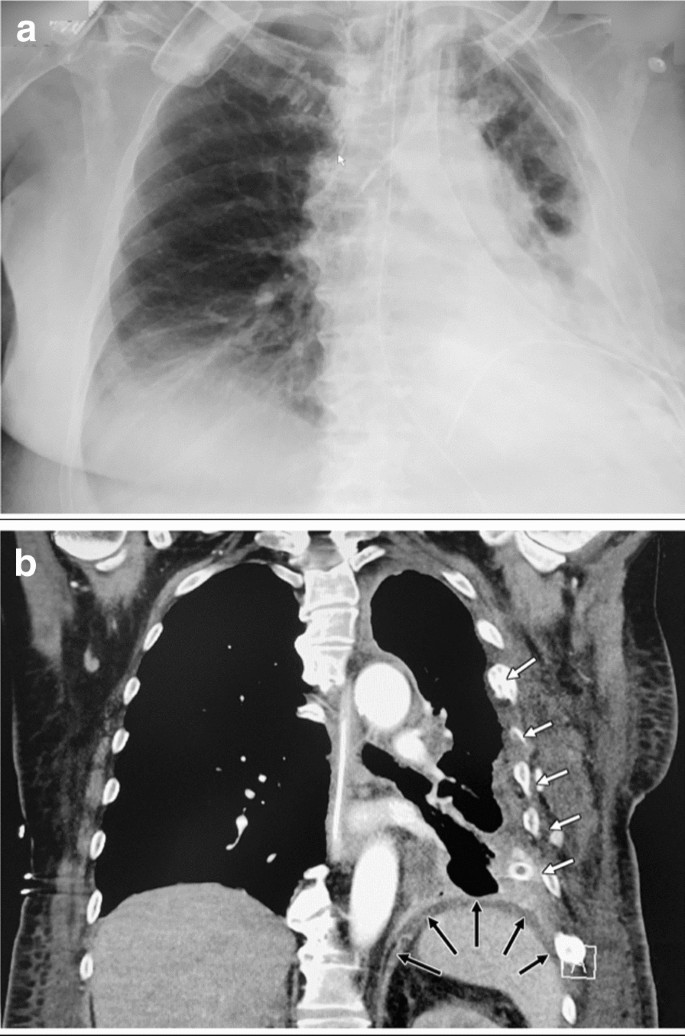

Radiological imaging on day 20. Chest X-ray examination (a) and thoraco-abdominal CT scan (b): reaccumulation of the left pleural empyema. The diaphragm stayed intact (black arrows) over the whole clinical course subsequent to reconstruction during initial surgery on day 1. White arrows indicate remnants of the healed rib fractures as a consequence of the bicycle trauma 7 months prior to admission for feco-pneumothorax

Radiological imaging on day of admission. Thoraco-abdominal CT scan with localizer of carried out CT scan (a) and representative CT scan images (b, c): enterothorax with splenic flexure prolapse through an old undetected traumatic rupture of the left diaphragmatic center, consecutive colic incarceration (b + c; arrows) with ischemia, rupture of the colon into the left pleural cavity with feco-pneumothorax under tension, cardiac depression due to mediastinal shift to the right and sepsis secondary to left pleural empyema (c), inversed diaphragm and midline shift to the right (a + b). Post-surgical chest X-ray examination (d): re-expanded left lung and reversal of the mediastinal shift with reconstructed diaphragm